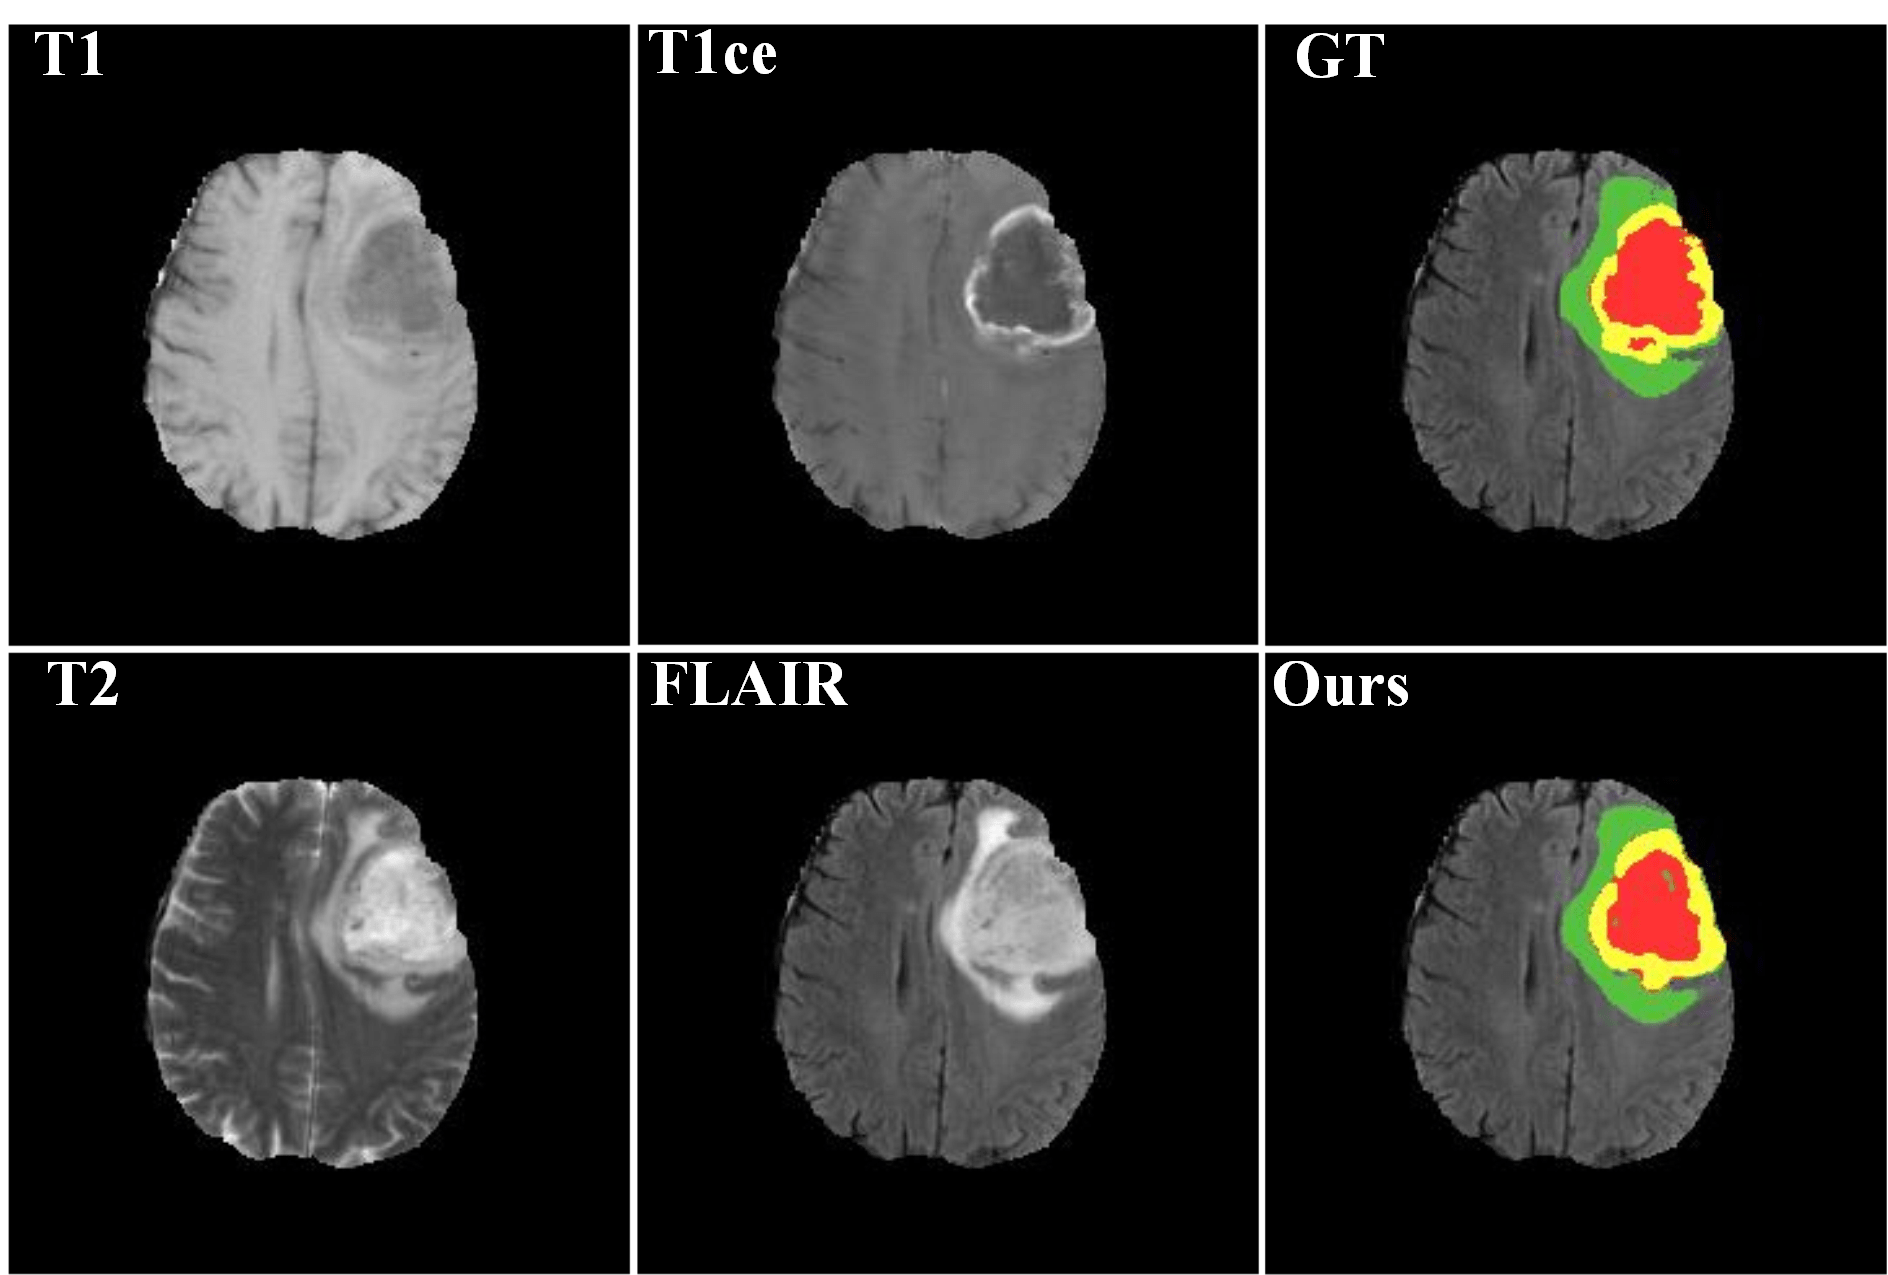

Automated segmentation of brain tumors in 3D magnetic resonance imaging plays an active role in tumor diagnosis, progression monitoring and surgery planning. Based on convolutional neural networks, especially fully convolutional networks, previous studies have shown some promising technologies for brain tumor segmentation. However, these approaches lack suitable strategies to incorporate contextual information to deal with local ambiguities, leading to unsatisfactory segmentation outcomes in challenging circumstances. In this work, we propose a novel Context-Aware Network (CANet) with a Hybrid Context Aware Feature Extractor (HCA-FE) and a Context Guided Attentive Conditional Random Field (CG-ACRF) for feature fusion. HCA-FE captures high dimensional and discriminative features with the contexts from both the convolutional space and feature interaction graphs. We adopt the powerful inference ability of probabilistic graphical models to learn hidden feature maps, and then use CG-ACRF to fuse the features of different contexts. We evaluate our proposed method on publicly accessible brain tumor segmentation datasets BRATS2017 and BRATS2018 against several state-of-the-art approaches using different segmentation metrics. The experimental results show that the proposed algorithm has better or competitive performance, compared to the standard approaches.